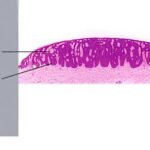

All types of seborrheic keratosis have in common hyper-keratosis, acanthosis, and papillomatosis. The acanthosis in most instances is due entirely to upward extension of the tumor. Thus the lower border of the tumor is even and generally lies on a straight line that may be drawn from the normal |

epidermis at one end of the tumor to the normal epidermis at the other end . Two types of cells are usually seen in the acanthotic epidermis: squamous cells and basaloid cells. The former have the appearance of squamous cells normally found in the epidermis; the basaloid cells are small and uniform in appearance and have a relatively large nucleus. In areas of slight intercellular edema, intercellular bridges can be easily recognized . Thus they resemble the basal cells found normally in the basal layer of the epidermis. |